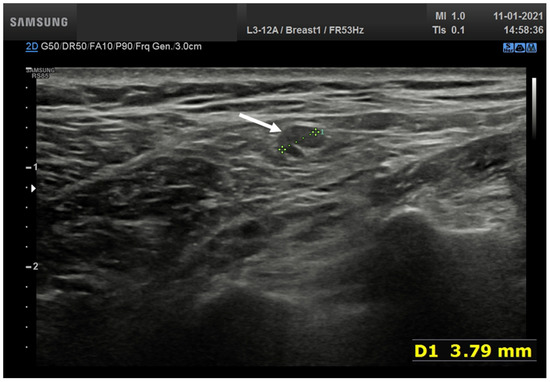

In total, four nodes (6.9%) showed huge reduction and displacement of the echogenic hilum and round or oval shape (Figure 4).

Figure 4.

(a) Hypoechoic lymph node round shape without hilum (arrows) in laterocervical side; (b) Hypoechoic lymph node oval shape without hilum (arrow) in laterocervical side; (c) Axillary small hypoechoic lymph node oval shape without hilum (arrow).